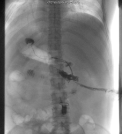

本次交流的重点病例是一名车祸伤术后多发肠瘘、腹腔出血、腹腔开放的34岁青年男性,车祸伤急诊手术后出现并发症,在25天内因为反复肠瘘、腹腔出血又被迫进行了四次急诊腹部手术,最终导致了严重的多发肠瘘及腹腔开放,于2018年1月25日转来我院重症监护病房。入院后经过水电解质紊乱纠正、脏器功能维持、腹腔感染控制,病情得到逐步控制后转回胃肠外科病房进行后续的冲洗引流、营养支持等综合治疗,使得腹壁创面逐步缩小,患者体力明显改善。

经过了充分的术前评估和讨论后于2018年8月21日进行确定性手术治疗,手术过程是惊心动魄的一天,手术难度非常大,包括复杂肠粘连松解、多发肠瘘切除、消化道重建与腹壁重建,手术历时10个小时。手术的难点是十二指肠瘘和腹壁缺损的处理。因为十二指肠瘘口范围较大,而且是炎性瘢痕组织,不能单纯缝合,十二指肠切除极有可能造成危及病人生命的大出血,因此李元新主任游离了一部分小肠与十二指肠瘘口吻合,并预想到术后会发生吻合口瘘,因此在吻合口周围放置好引流管,术后虽然确实发生了十二指肠瘘,但经过保守治疗最终用生物蛋白胶进行封堵成功。

另一手术难点是腹壁重建,因为本病人经历多次手术,两侧腹壁及胸壁瘢痕组织严重,加之多次放置多跟引流管,导致腹壁两侧无法游离及转移皮瓣,导致皮肤无法关闭,李元新主任手术团队再次应用大网膜替代皮肤组织的策略成功关闭患者腹腔,避免了诸多相关并发症的再次发生。